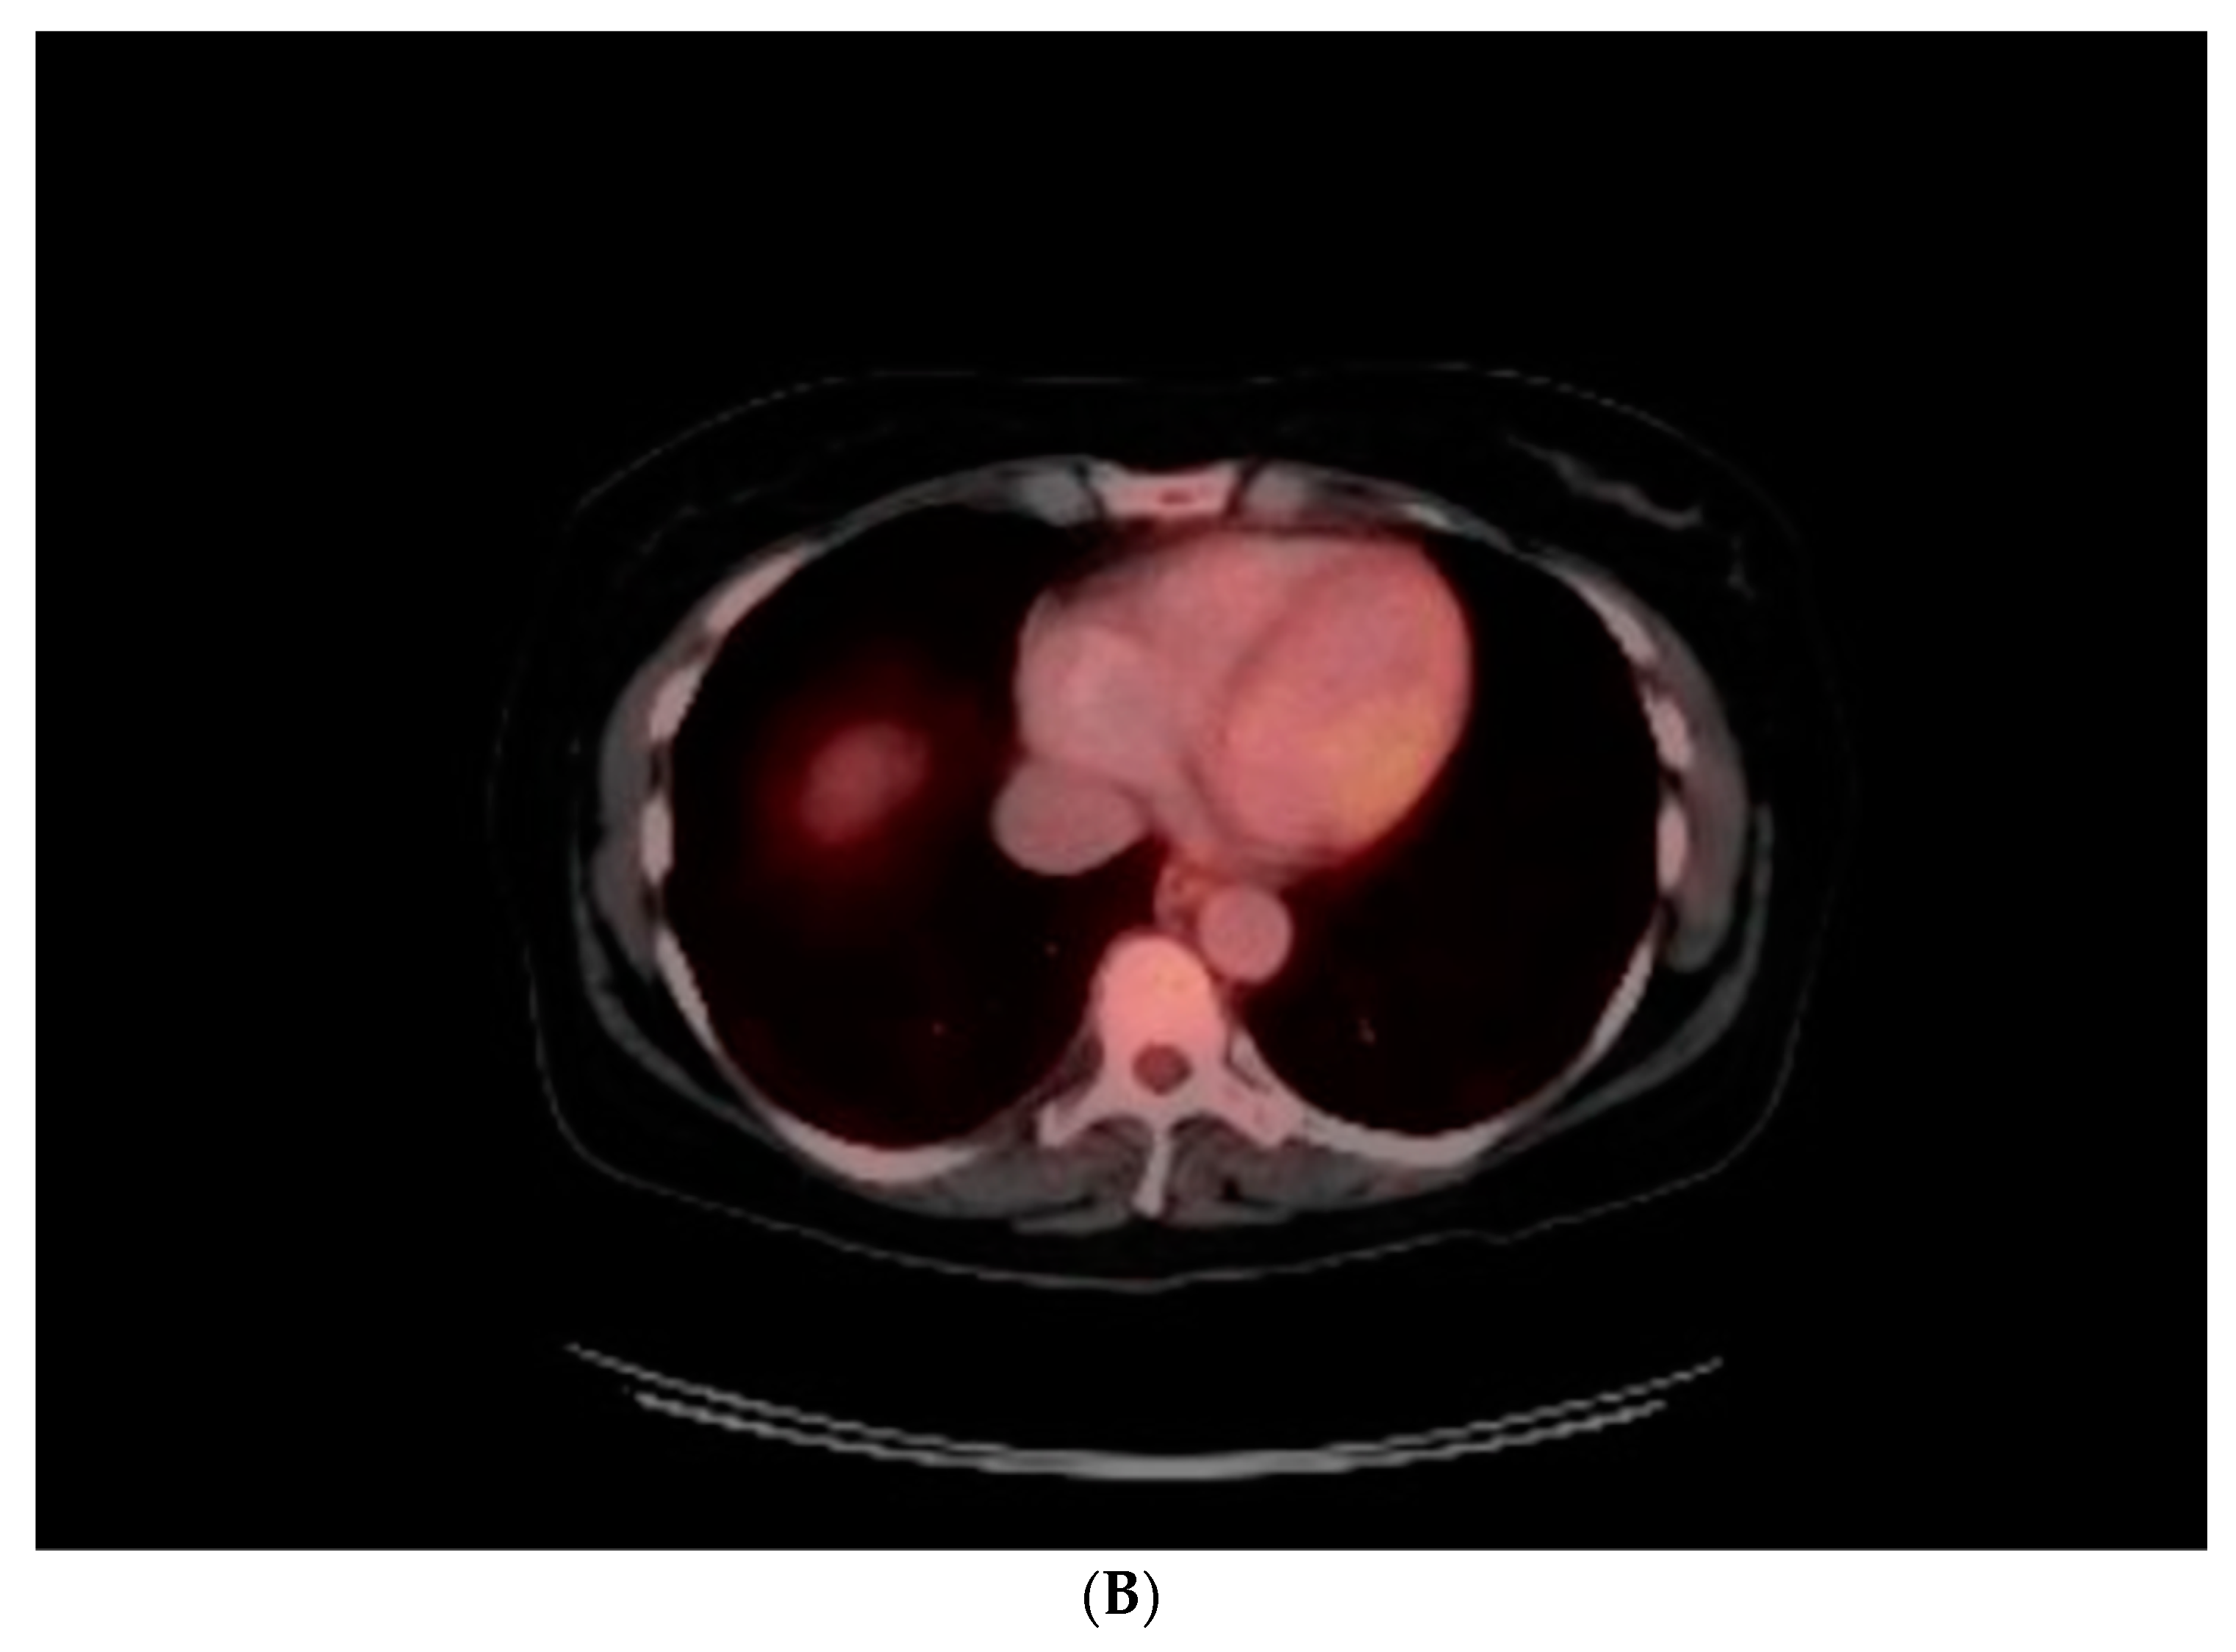

The angiographic findings suggested external compression as the likely cause of the 80% lesion in the mid LAD. This assumption gained credence when considering the non-invasive imaging results. Transthoracic echocardiogram showed normal left ventricular chamber diameter and systolic function with an ejection fraction of 50-55%, but was significant for notable septal wall thickening (Figure 3A–C). A subsequent PET/CT scan demonstrated an FDG-avid focus aligning with a heterogeneously enhancing mass along the interventricular septum of the heart, measuring approximately 3.1 x 2.8 cm, representing a significant change from her previous scan (Figure 4A,B). A post-procedural CT scan, performed after the emergent coronary angiogram and pacemaker implantation, revealed significant interventricular septal thickening corresponding to myocardial metastases (Figure 5A), a contrast to a CT performed approximately five months prior, which indicated normal septal thickness (Figure 5B).

Figure 4. A: Positron emission tomography with fluorodeoxyglucose (FDG) uptake in the interventricular septum (red arrow) consistent with metastases from known cervical cancer, correlating with TTE findings above. B: Prior PET (3-4 months prior).